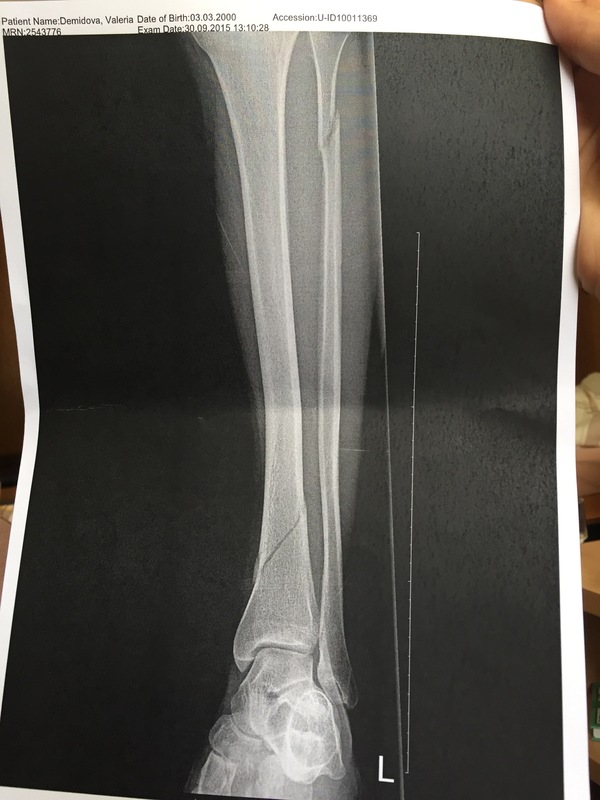

Мы прилетели в госпиталь,меня положили в палату где все белое и от этого становится еще более не по себе.Мне порезали термобелье,потому что не было сил терпеть, когда его снимают с больной ноги.Повезли на рентген,сделали,но ничего не сказали и снова отвезли в палату,в ожиданиях снимка.За этот период времени успела пару раз всплакнуть и задуматься о том,как сказать родителям о травме(как оказалось легче,чем думала).Принесли снимок

Доктор сказал "Есть два выхода из ситуации-это гипс или пластина,но я не вижу смысла в лишний раз травмировать кожу,т.к. сращивание в обоих случаях 6 недель,но после второй операции нужно время". Мы согласились с его ходом мыслей и положили гипс.Через неделю мы уезжали домой и врач сказал сделать повторный рентген через 4-6 недель.

Я отдыхала дома с гипсом на ноге,надеясь что скоро его снимут. Через 3 недели после травмы я поехала в больницу на рентген,при получении снимка я,естественно,сразу посмотрела на него.Моему удивлению не было предела,когда я увидела тоже самое что и в день падения только смещение больше.Теша себя надеждой что "все так и должно быть" пошла к травматологу,который отправил нас к заведующему отделению со словами "я думаю,что нужна операция,но заведующий знает лучше,что делать".Мы поднялись наверх,зашли в кабинет.Я отдала снимки доктору,он подняв их напротив лампы однозначно сказал "операция",на доли секунды в кабинете затаилась тишина,как он снова продолжил "Место перелома,слишком низкое-нижняя треть голени,кровоснабжение в этом месте в организме самое маленькое,с гипсом сращиваться кость будет год,если не больше,а с пластиной/штифтом 3 месяца.На госпитализацию".Мало того,что мне сделают операцию,так я ещё 3 недели с гипсом в пустую ходила.Наверное,все что не делается все к лучшему.